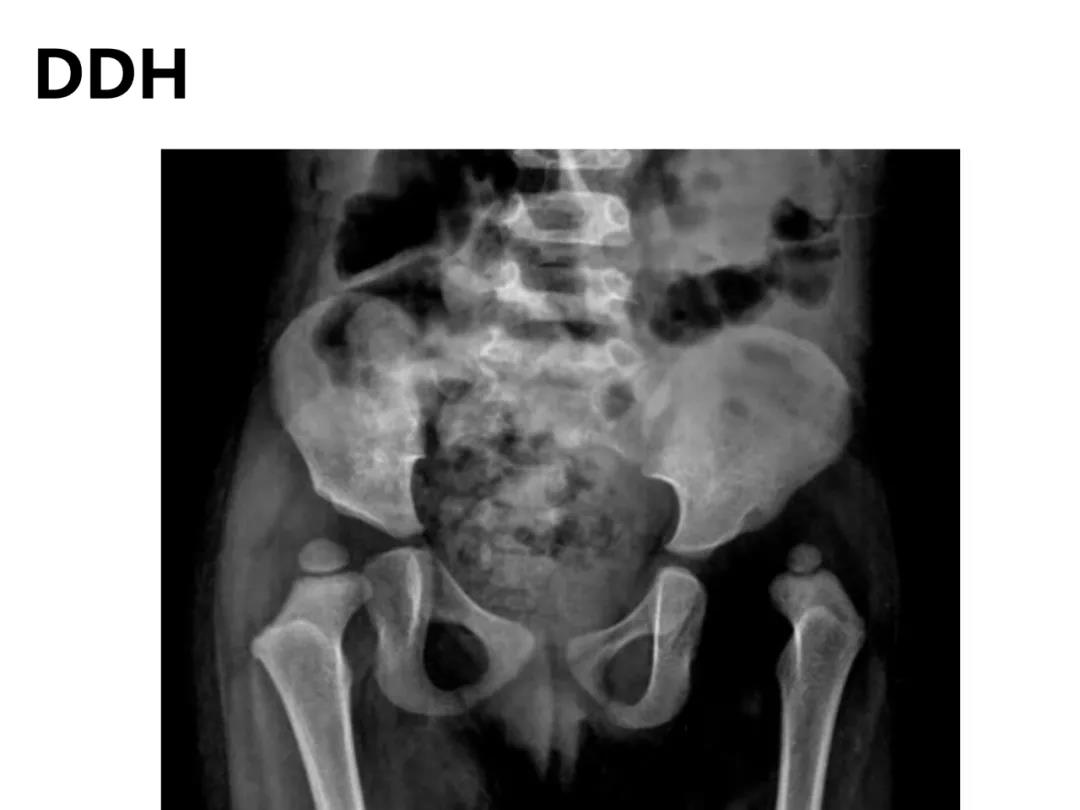

小儿骨科X线片汇总,临床读片宝典!